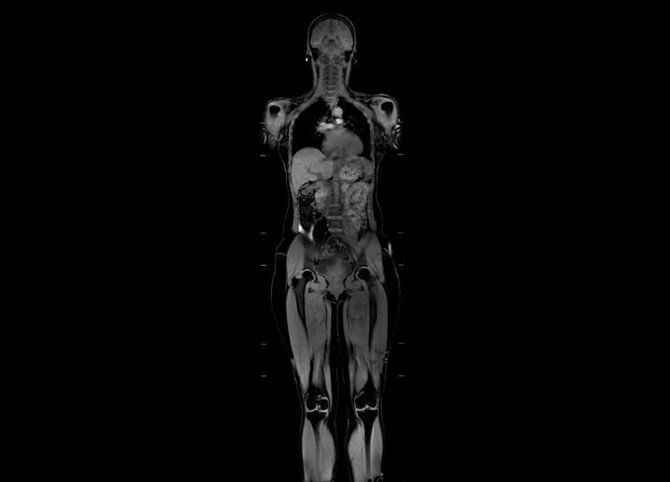

Meet our next-generation SIGNA MRI scanners & solutions

SIGNA MRI Scanners

Our 1.5T, 3T, PET/MR and 7T scanners deliver the latest in imaging innovation with AIR Recon DL, and AIR Coils.